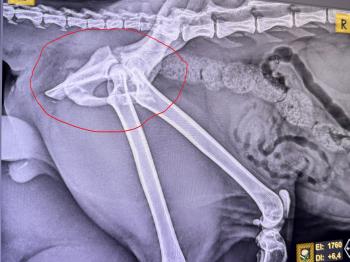

Die Untersuchungen bestätigten den ersten Verdacht: Castor war von einem Fahrzeug angefahren worden. Sein Körper trug Spuren seines harten Lebens – frische Wunden und alte Narben erzählten die Geschichte eines Straßenkämpfers, der trotz allem nicht aufgegeben hatte.

Doch damit nicht genug. Bei einem Krankheitstest wurde zudem festgestellt, dass Castor positiv auf Katzen-Immunschwäche (FIV) ist. Das schmälert natürlich seine Vermittlungschancen. Außerdem hat er eine komplizierten Beckenfraktur, die eine schwere Operation erforderlich macht. Glücklicherweise hat er Blase und Darm unter Kontrolle und ist in der Lage, die Katzentoilette zu benutzen.